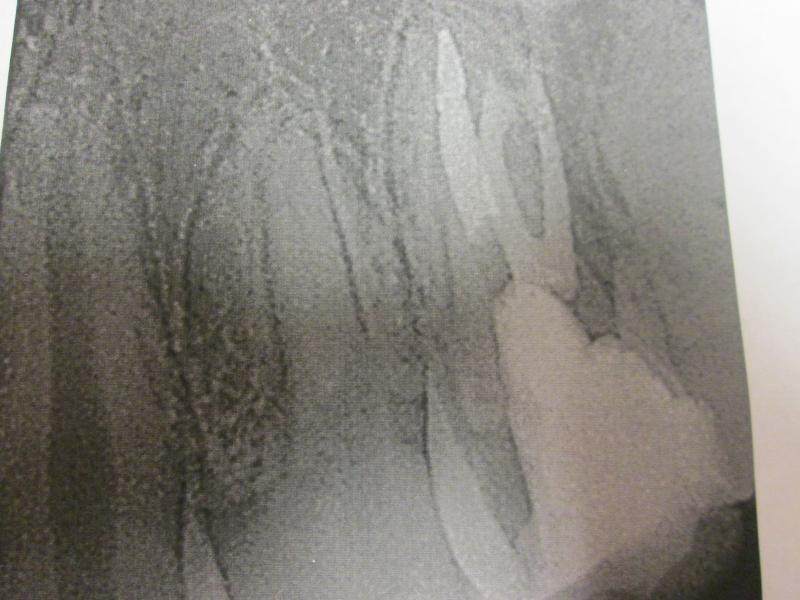

DR JET LOVES ROOT CANALS

"DR. JET'S MISSION IS TO PERFORM  ROOT CANALS FOR A REDUCED FEE USING THE LATEST TECHNOLOGY  AND TECHNIQUES TO SERVICE THE MANY PEOPLE WHO ARE UNINSURED OR UNDER-INSURED GIVING EVERYONE AN OPPORTUNITY TO SAVE THEIR TOOTH!"

ROOT CANALS by DR. JET (Jetepon Chiranand DDS)